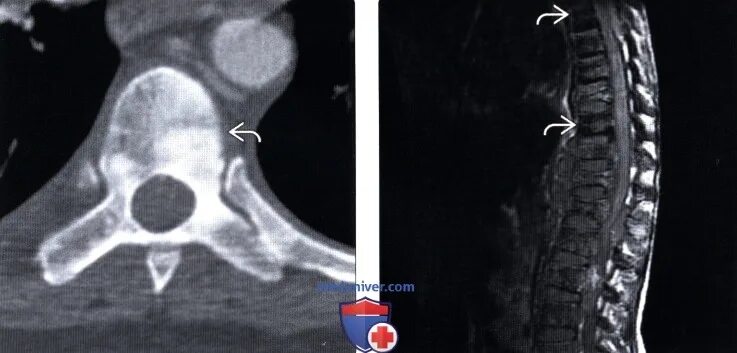

Метастазы в костном мозге